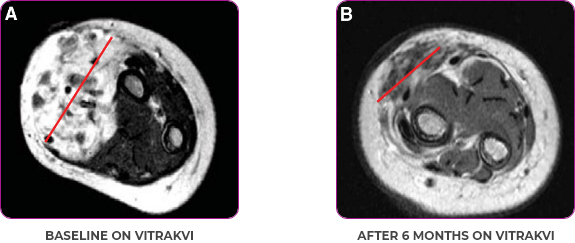

PATIENT CASE:

INFANTILE FIBROSARCOMA

OF SOFT TISSUE1

- 5-month-old with IFSa

- Progression after chemotherapy

- Confirmed PRa after 4 cycles of VITRAKVI® (larotrectinib)

- Referred for definitive limb-sparing surgery after 6 cycles

of VITRAKVI; achieved pCRa,b

Response to VITRAKVI1

- Patient achieved a confirmed partial response after 4 cycles of VITRAKVI with a 45% reduction in tumor burden

- Following 6 cycles of VITRAKVI, the patient was referred for definitive limb-sparing surgery

- Pathology revealed a complete pathologic response and clear resection margins with scar tissue noted

Reduction in tumor burden1

MRIa imagery of the brain. Red line indicates the maximum dimension.1

aMRI, magnetic resonance imaging.

Pre- and post-treatment imaging, by DuBois SG et al, is licensed under CC BY 4.0.